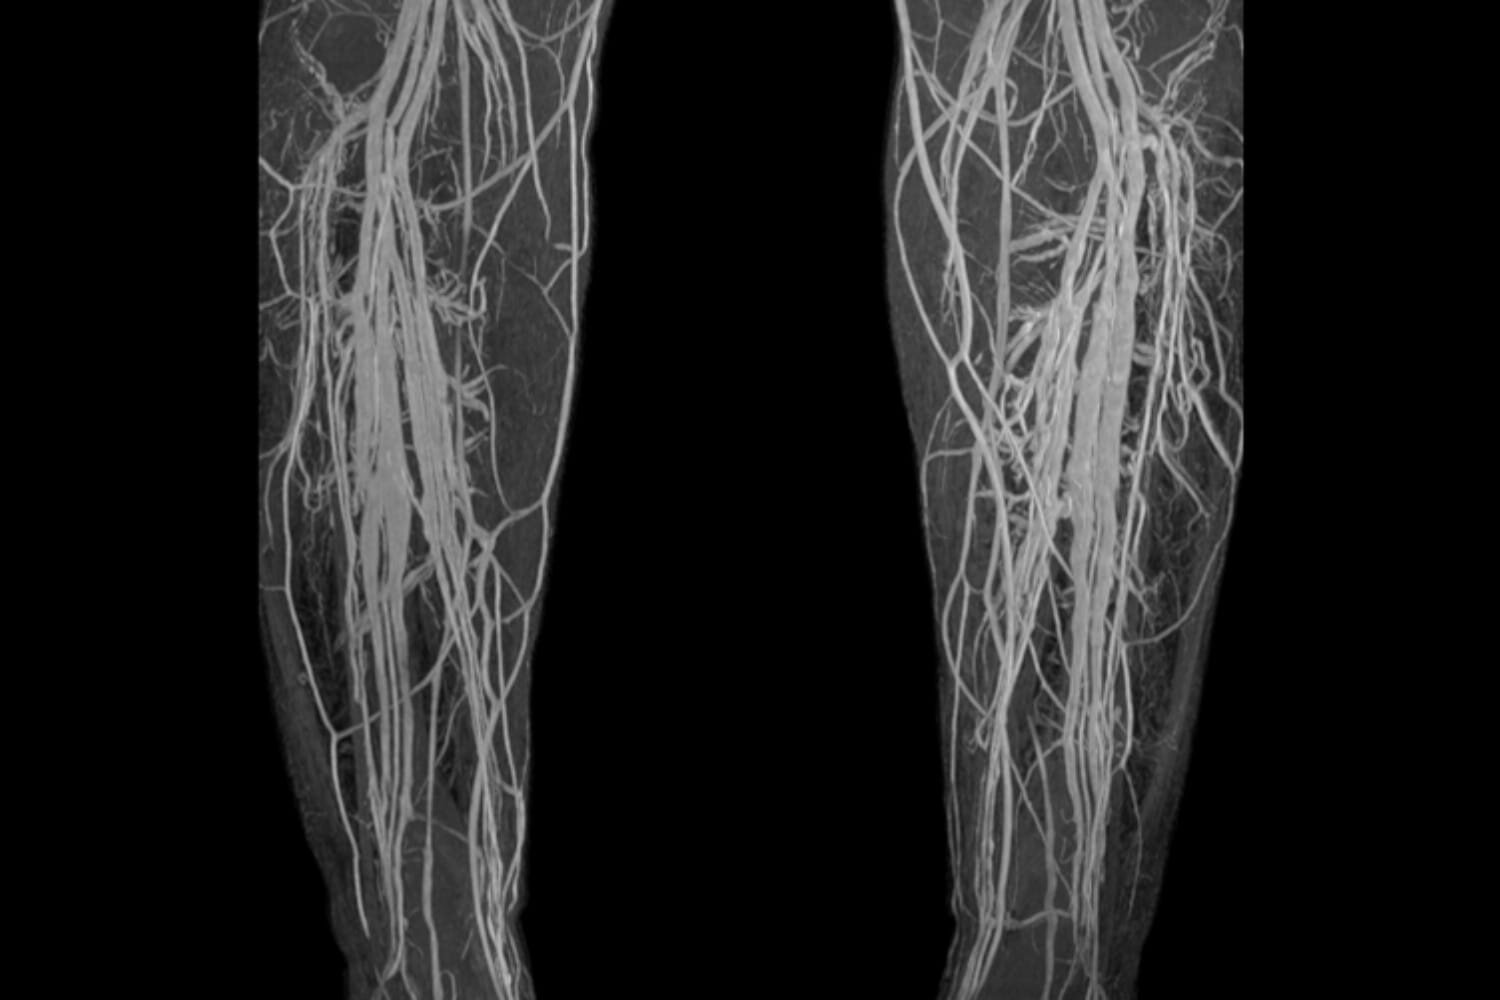

Figure 3 from Deep vein thrombosis using noncontrastenhanced MR What Is A Mri Venogram It may or may not require the injection of a contrast. A diagnostic procedure that uses a combination of a large magnet, radiofrequencies, and a computer to produce detailed images of organs and. Providers use this test to diagnose deep. A venogram is a test done by injecting contrast dye into your veins. Magnetic resonance (mr) venography is uniquely suited. What Is A Mri Venogram.

[PDF] MR Venography for the Assessment of Deep Vein Thrombosis in Lower What Is A Mri Venogram Providers use this test to diagnose deep. It may or may not require the injection of a contrast. A venogram is a test done by injecting contrast dye into your veins. Magnetic resonance (mr) venography is uniquely suited for evaluation of the veins of the abdomen, thorax, and extremities, as no ionizing radiation is used and contrast. A specific type. What Is A Mri Venogram.